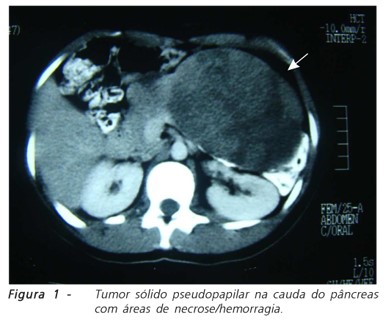

Tumor Sólido-Cístico Pseudopapilar – (TSCP) ou Tumor Papilar Sólido-Cístico (TPSC)

Ele é raro e de baixo grau de agressividade, mas metastisa para o fígado. Representa de 1 a 3% de todos os tumores pancreáticos e sua incidência tem aumentado na última década. Foi descrito em 1959 por Frantz, por isso também conhecida por Tumor de Frantz. Apresenta ambas as áreas sólida e cística que podem corresponder a degeneração do tumor, necrose ou hemorragia.

Frequentemente observado:

- mulheres entre 22 a 38 anos;

- acomete qualquer local do pâncreas, mas mais comumente atingem a cauda pancreática;

- 80% dos casos, os doentes apresentam sintomas como dor abdominal ou sensação de “inchaço” ou massa;

- Os marcadores tumorais no sangue em geral estão normais como AFP (alfa-fetoproteína), CEA, CA 19,9 e Ca 125;

- tomografia ou ressonância mostram massa sólido-cística bem definida, arredondada eventualmente com calcificação, hemorragia intra-tumoral, degeneração cística e realce heterogêneo com administração do contraste endovenoso;

- eco-endoscopia com biópsia só dá o correto diagnóstico em 50% dos casos. A imuno-histoquímica das células tumorais são positivas principalmente para vimentina, CD10, CD56, neuro-enolase, alpha1antitripsina e Beta-catenina.

O tratamento é a retirada cirúrgica e as chances de cura podem atingir 95% nos tumores totalmente retirados. Mesmo com metástases hepáticas ganho de sobrevida pode ser observado quando são retirados tanto o tumor primário pancreático quanto as metástases hepáticas. Habitualmente não respondem a quimioterapia ou radioterapia.